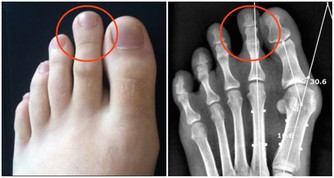

3、脾臟有毒:商丘穴

脾臟有毒時,面部會呈現色斑,並且白帶過多,身上會堆集脂肪,致使肥壯。

用手指按壓商丘穴,酸重感即可,一次三分鐘即可。